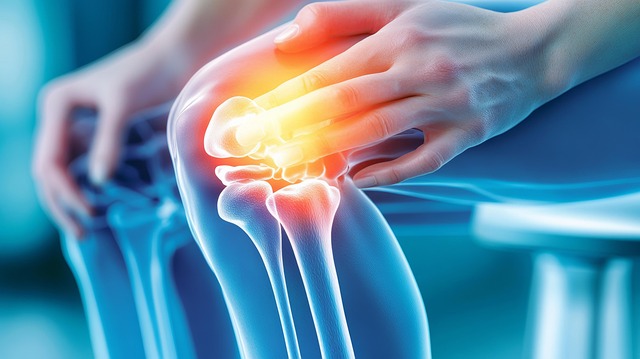

5. 무릎 통증 동반

고관절 문제는 무릎에도 영향을 미쳐 무릎에 통증을 유발할 수 있습니다. 이는 고관절과 무릎의 기능적 연관성 때문입니다.